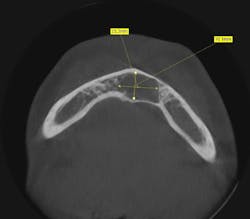

Clinically, there was no buccal or lingual expansion (figure 1). The patient’s medical history was noncontributory. A CT scan revealed a 1.5 cm x 1 cm well-defined, circular, hypodense area inferior to the lower incisors (figures 2–4).